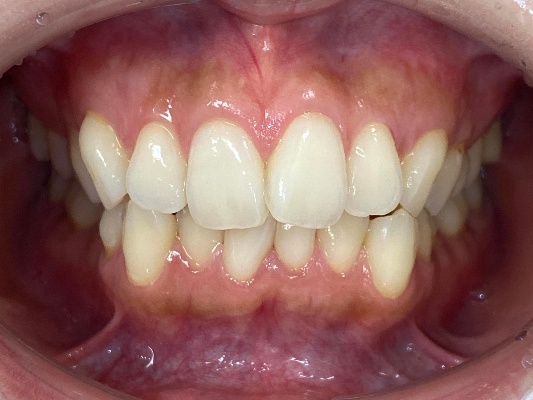

来院時の歯並び写真

上下前歯の歯並びがガタガタしているのが気になる、きれいにしたいとのご希望で来院されました。